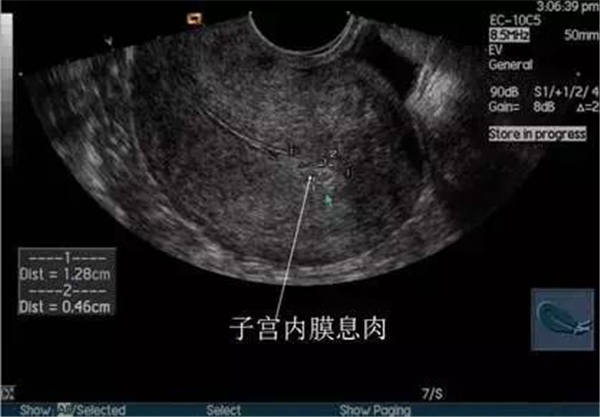

2、宮腔積血、積膿、積液

(宮腔積液)